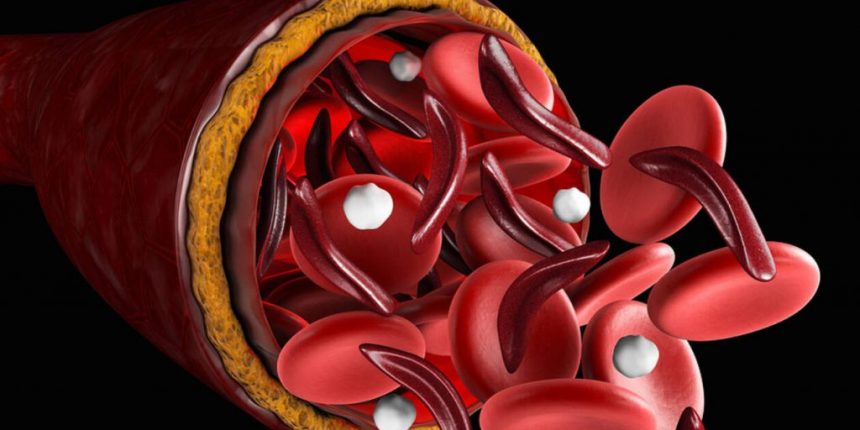

Αποθηκεύεται στους ιστούς κυρίως με την μορφή της φεριτίνης, απορροφάται από την τροφή στο λεπτό έντερο και περνά στο αίμα και στον μυελό των οστών. Εκεί χρησιμοποιείται στην παρασκευή αιμοσφαιρίνης, η οποία ενσωματώνεται στα ερυθρά αιμοσφαίρια.

- Αυξάνεται ο κίνδυνος καρδιακών παθήσεων. Η έλλειψη σιδήρου μεταβάλλει τον αριθμό των ερυθρών αιμοσφαιρίων και δυσκολεύει την κυκλοφορία του οξυγόνου στα όργανα.

- Η έλλειψη σιδήρου προκαλεί μείωση στον αριθμό και το μέγεθος των ερυθρών αιμοσφαιρίων, με αποτέλεσμα το δέρμα να γίνεται πιο χλωμό.

Ο Σίδηρος ανήκει στην κατηγορία των μετάλλων. Πρόκειται για ένα στοιχείο εξέχουσας σημασίας για τον οργανισμό . Γενικά, συμβάλλει στο σχηματισμό των ερυθρών αιμοσφαιρίων και της αιμοσφαιρίνης, στη μεταφορά του οξυγόνου στο σώμα, ενισχύει τη ζωτικότητα και την ενέργεια, ενώ μειώνει την πνευματική και σωματική κόπωση. Η μεταφορά του οξυγόνου στο σώμα πραγματοποιείται μέσω μιας πρωτεΐνης, της αιμοσφαιρίνης, που βρίσκεται στα ερυθρά αιμοσφαίρια. Σημαντικό συστατικό για τη δημιουργία της πρωτεΐνης αυτής είναι ο σίδηρος. Η αποθήκη του σιδήρου στο σώμα είναι η φερριτίνη, η οποία βρίσκεται στα κύτταρα του σώματος. Η φερριτίνη απελευθερώνει ελεγχόμενα ποσότητες σιδήρου ανάλογα με τις ανάγκες του οργανισμού.

Ο σίδηρος συμβάλλει στη μεταφορά οξυγόνου και στη διάπλαση του αίματος. Με ανεπαρκή σίδηρο παράγεται λιγότερη αιμοσφαιρίνη. Η αιμοσφαιρίνη μεταφέρει το οξυγόνο που έχουμε εισπνεύσει και είναι απαραίτητο στα κύτταρα για τις μεταβολικές τους διεργασίες, από τους πνεύμονες σε ολόκληρο το σώμα.